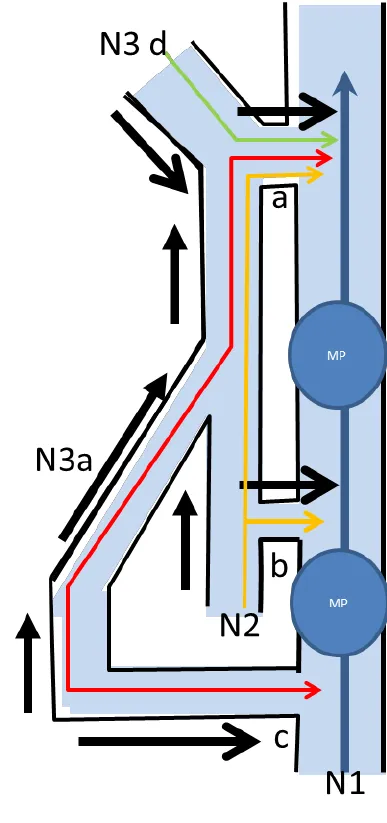

TIPS: 下肢静脉层级网络

覆盖隐静脉表面的筋膜称为“隐筋膜”,其与深筋膜之间的间隙称为“隐筋膜室”。下肢静脉至此刻划分为三个解剖层次,即:深层(深筋膜之下);筋膜间层(深筋膜与隐筋膜之间,即皮下深层)和皮下层(皮肤与隐筋膜之间,即皮下浅层)。

Franceschi和Zamboni将其称为解剖筋膜室 (anatomical compartment, AC),三层分别为AC1、AC2和AC3,其内走行的静脉分别为N1(深静脉系统)、N2(大隐静脉系统)和N3(大隐静脉属支)。

7. N3 (大隐静脉属支) 的治疗

N3静脉的治疗取决于它们的大小、分布以及它们对任何潜在静脉反流治疗的反应。大的静脉曲张可以在消融N2静脉干或IPV时通过静脉切除术去除,也可以留置观察是否可以自行消退,为有需要的患者保留延迟静脉切除术。

5. 穿支静脉反流 (PVR) 的治疗

许多医生忽略了作为静脉反流模式的一部分的IPV。1985年以前,除了开放结扎术外,没有其他治疗方法。然而,1985年Hauer发明了筋膜下内镜穿支静脉(subfascial endoscopic perforating vein, SEPS)手术,将内镜引入膝下筋膜下间隙,在筋膜下夹闭静脉。然而,SEPS仍需要2 ~ 3 cm的切口,通常需要全身麻醉,术后肌肉操作带来的不适较多,且穿支血管的处理局限在小腿内侧。2000年,发明了经腔穿支静脉闭塞 (TRansluminal Occlusion of Perforators, TRLOP) 手术。

在超声控制下,对IPV进行插管,并在穿支置入消融装置。最初使用射频,后来使用腔内激光。TRLOP在2007年被“重新定义“为“穿支消融术“ (PAPS),尽管两种技术之间没有任何差异。其他工作者通过注射氰基丙烯酸酯胶进一步改进了这一点。TRLOP方法可与这些方法中的任何一种一起用于IPV的局部消融,即使静脉较短。